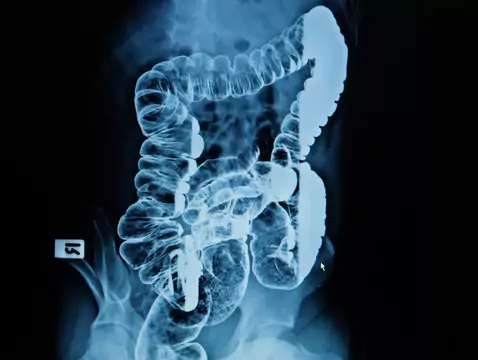

La angiodisplasia intestinal se clasifica como una malformación vascular que afecta a los intestinos. Muchos pacientes acuden a un especialista gastrointestinal con hemorragias extrañas e...

El estreñimiento es un problema que afecta no sólo a los adultos sino también a los niños. El estreñimiento se define como un trastorno del movimiento intestinal que implica la evacuación infrecuente...